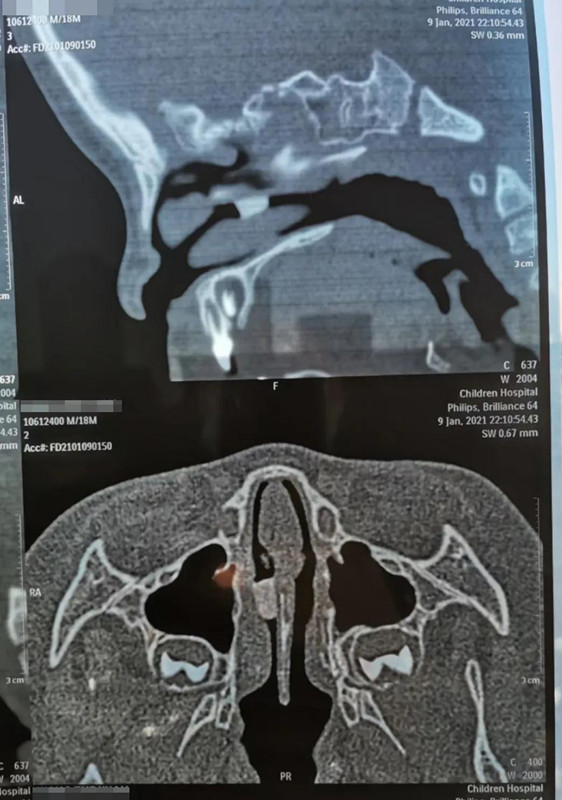

1月9日晚10点多,在夜深人安睡的时候,18个月男宝帅帅(化名)哭闹着被妈妈抱进啪啪网 就诊。妈妈说,晚上5点多,帅帅打碎了瓷鸭子玩具,偷偷把瓷鸭子嘴塞进鼻子里。经鼻腔三维CT重建,发现异物在右侧鼻腔较深位置,需次日全麻下手术取出。

取出8mm长异物